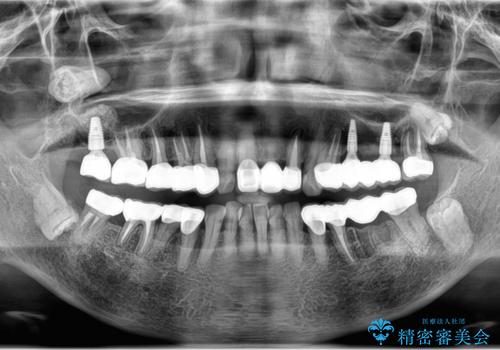

多発した虫歯による咬合崩壊 インプラントを用いた全顎治療

- 「これまで歯の治療をおざなりにしてしまい本当に後悔している。 時間と費用がかかってもいいので、しっかりと安心してかめるような状態にしてほしい。」、と全体的な治療を希望され来院されました。

歯の破折・再発した大きな虫歯・根尖病変・歯の欠損、これらの問題を根管治療・歯周外科・インプラント治療・セラミック補綴を行うことで一つづつ解決し安定した咬合状となるよう治療を進めます。